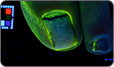

In a study of 11 patients, fluorescein was used to track the spread of the JUBLIA vehicle.

JUBLIA vehicle was shown to reach the infected nail bed1†

- Fluorescein was added to the vehicle solution to show the areas within the nail and nail bed where the solution was able to reach

- Photographs were taken 20-30 minutes after each application

- Two drops of the vehicle solution were applied only to the nail’s distal end. Unlike the JUBLIA application instructions, the vehicle in this study was not allowed to touch the top of the nail. For proper application instructions, click here1,3

†Note: Vehicle did not contain active ingredient efinaconazole; included dye for illustrative purposes only.